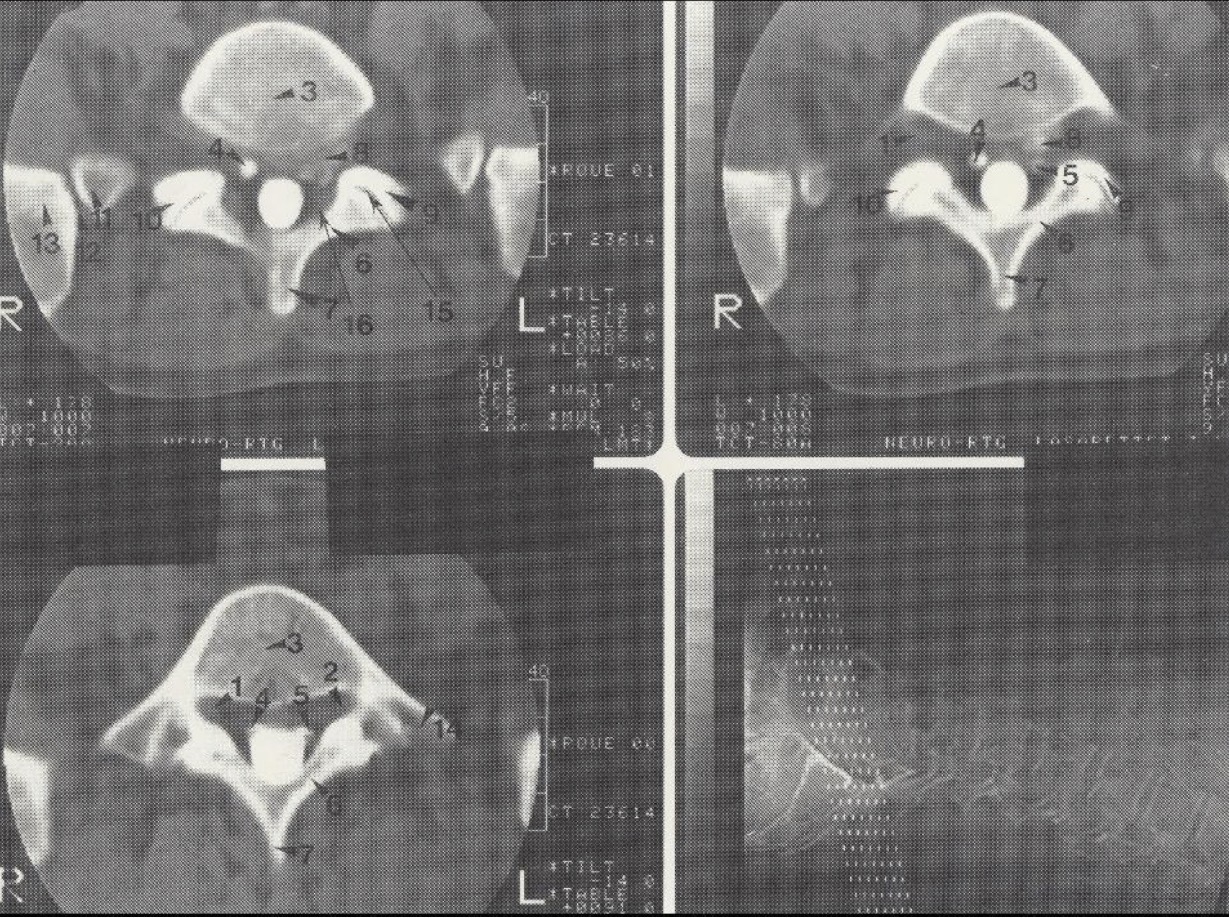

1

Dešinioji L 5 šaknelė

2

Kairioji L 5 šaknelė

3

Corpus vertebrae L V

4

Dešinioji S 1 šaknelė

5

Kairioji S 1 šaknelė

6

Lamina L V

7

Processus spinosus L V